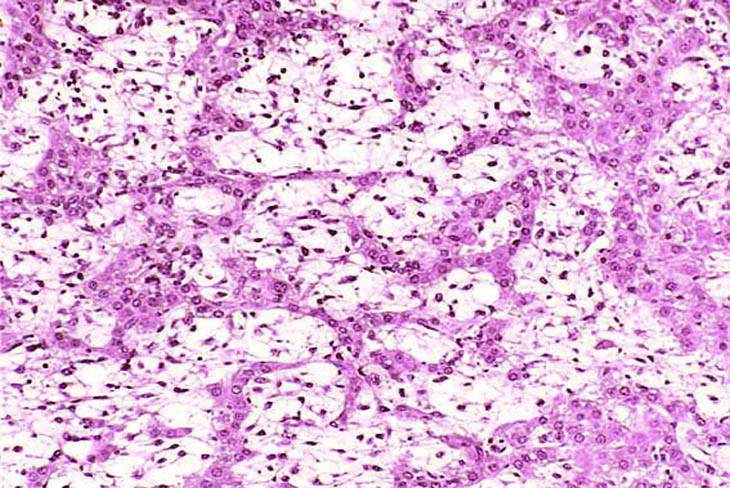

The proliferating stellate cells have a myxomatous appearance in some areas and have caused atrophy of hepatic cords.